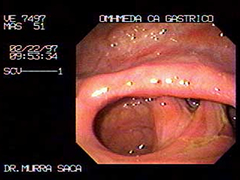

Paciente Masculino de 51 Años:

Hermano de prestigioso Cirujano Pediatra de El Salvador. El cual me solicita que le practique este estudio, le diagnosticamos este carcinoma obstructivo, la imagen endoscópica de control, Fue después de un año de habérsele diagnosticado por lo que Se le había practicado una derivación en omhmeda por haber sido irresecable al intento quirúrgico es de notar que esta imagen endoscópica es después de haber recibido quimioterapia y radiaciones con Cobalto.